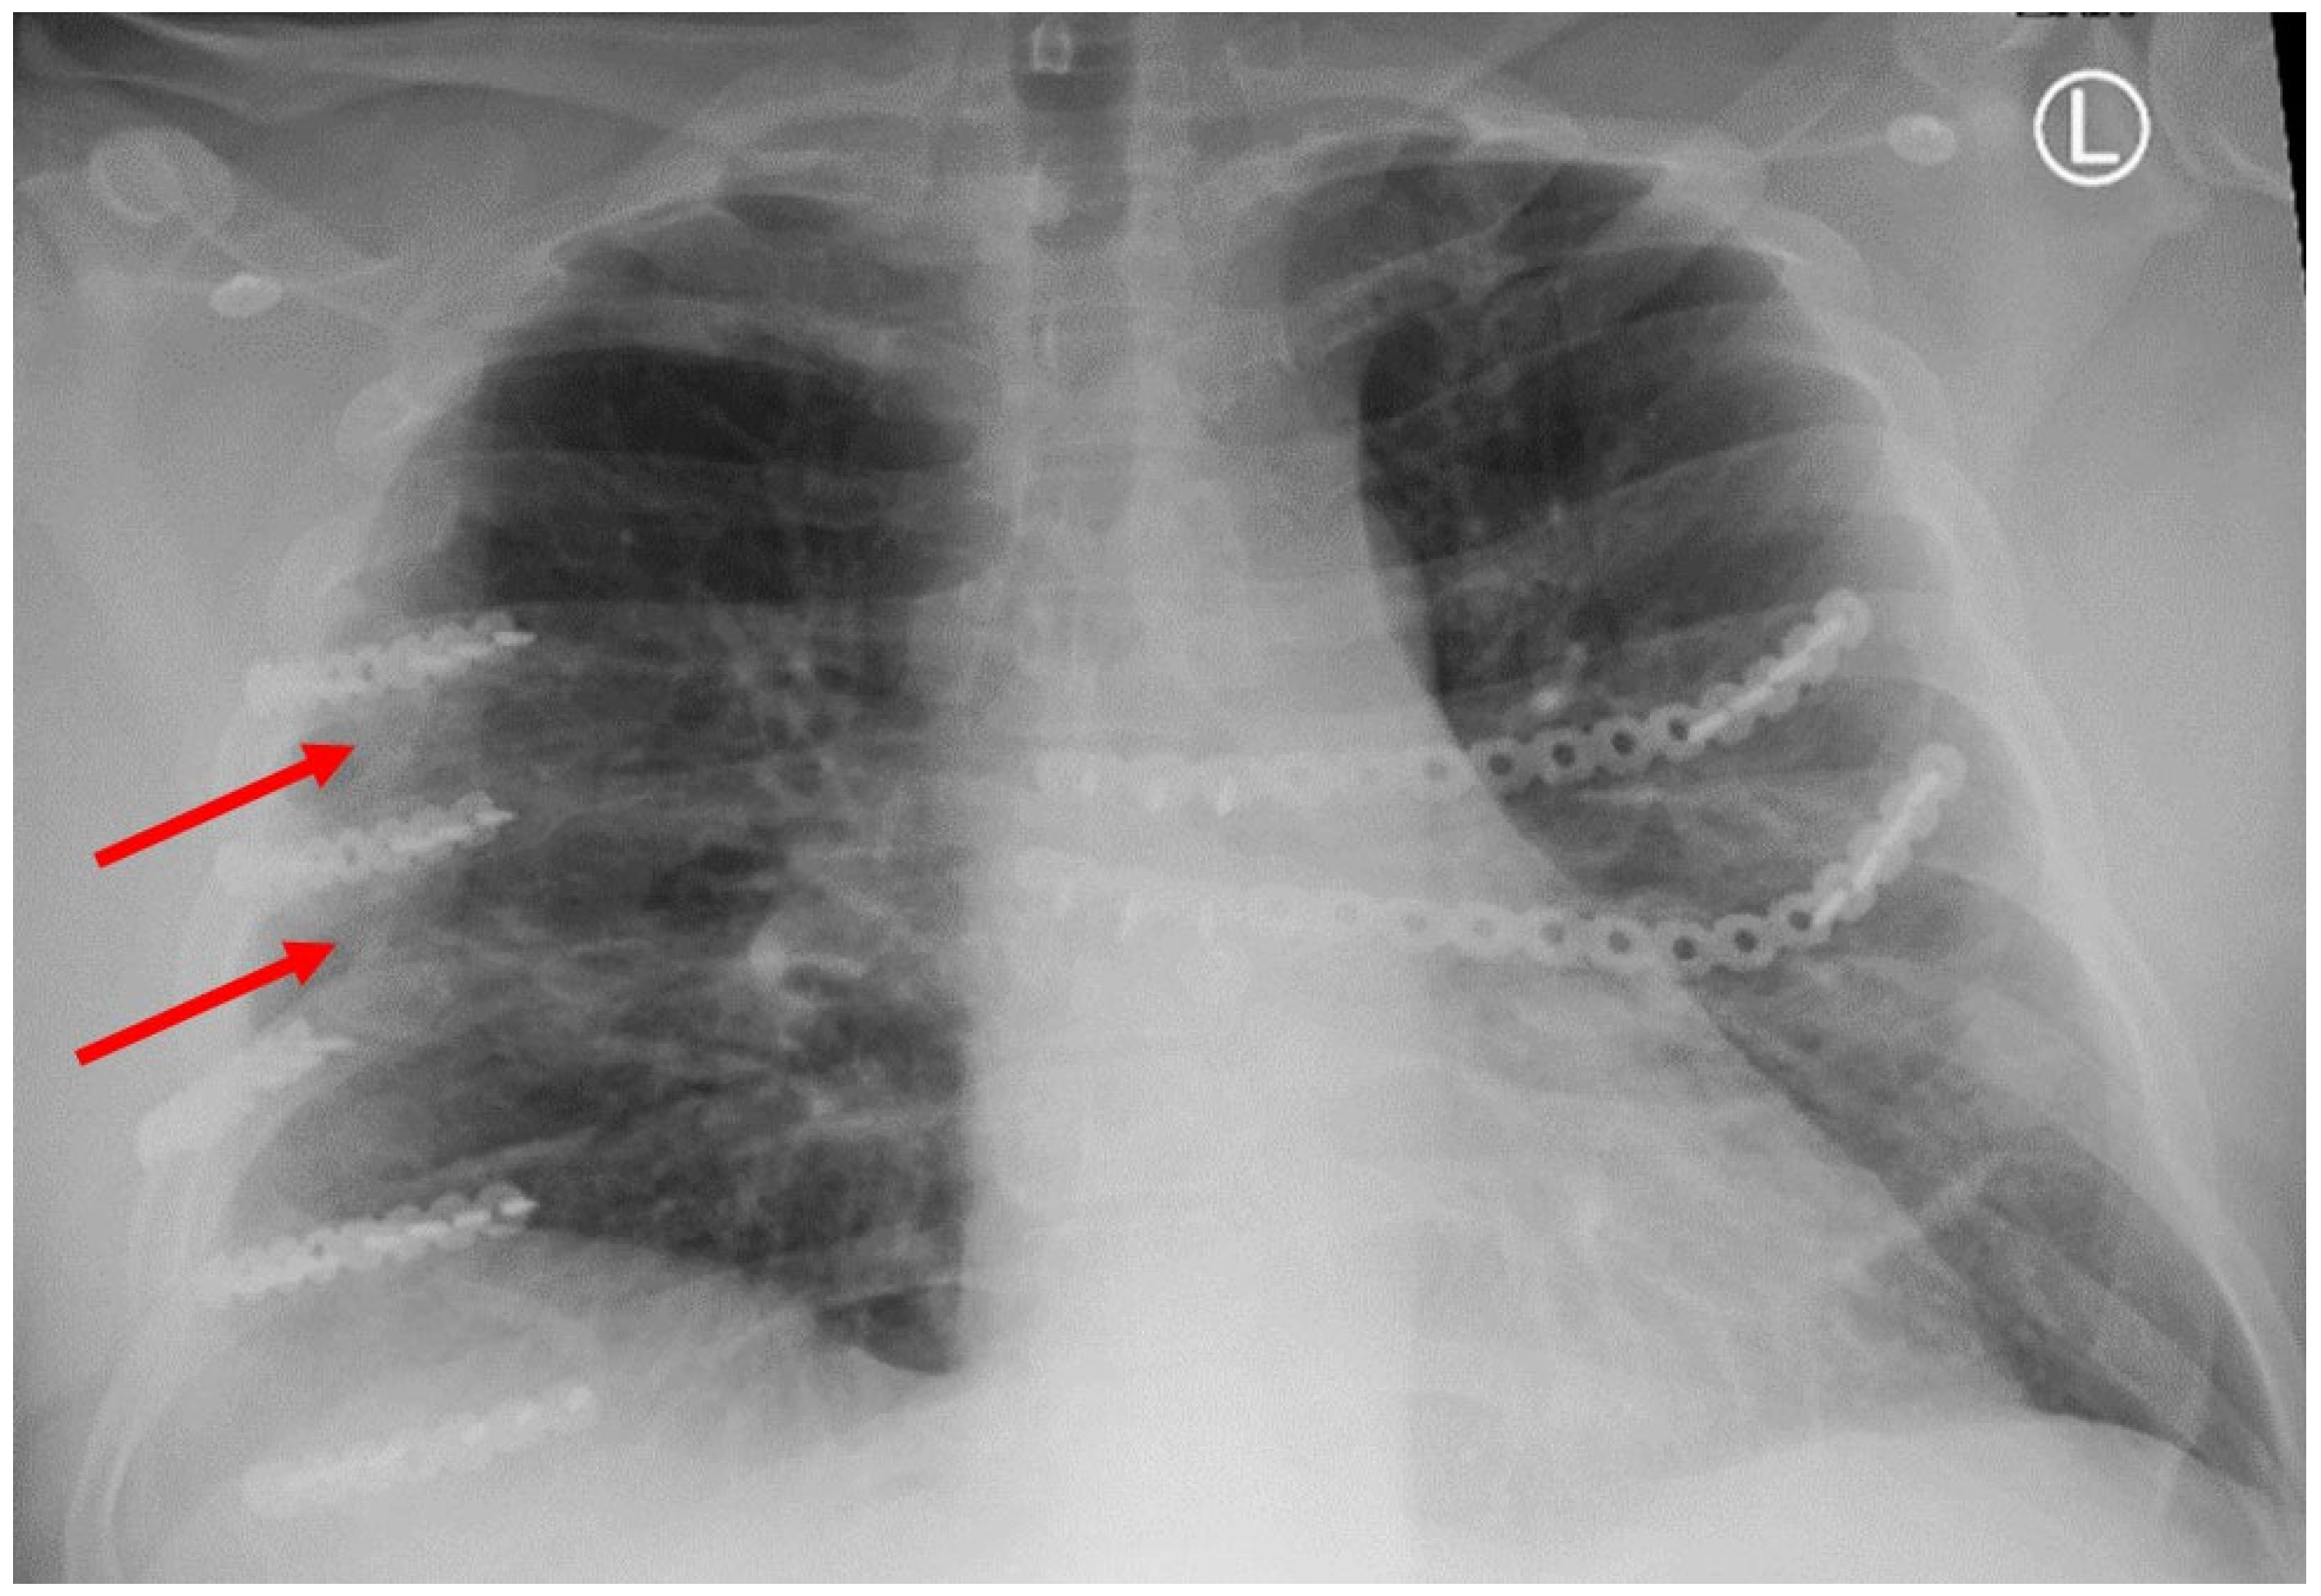

Figure 2. Three-dimentional reconstruction of CT scan with HO between ribs.

Patient-based variables were obtained from the medical records, including the following: age, race, gender, mechanism of injury, injury severity score (ISS), regional abbreviated injury severity score (AIS), medication administration, hospital length of stay, ICU length of stay, days of ventilator support, and discharge location. The existence of polytrauma was also evaluated, which was defined as any injury in a body region besides the chest with an AIS of 2 or greater. Rib fracture locations as well as displacement were characterized on initial CT scans based on their anatomical sector. These sectors consisted of the following: costal cartilage (CC); anterior (A) [rib costal cartilage junction to anterior axillary line]; lateral (L) [anterior axillary line–posterior axillary line]; posterior (P) [posterior axillary line to the lateral aspect of the paraspinus musculature]; and paraspinal (PS) [rib head–lateral aspect of the paraspinus muscles]. These anatomic divisions were used to further describe the location of SSRF titanium hardware on subsequent scans. All ribs were fixated using titanium plates with bicortical screw placement with a minimum of three screws anterior and posterior to the location of the fractures following the manufacturer’s guidelines. Both self-tapping (ST) and self-drilling (SD) screws were utilized as SD screws were not available until November 2019. ST screws require pre-drilling a bicortical osteotomy prior to placing the ST screw, which uses this pilot hole to guide its insertion into the rib. SD screws do not require this pilot hole to be drilled through the rib for fixation to occur. The number of plates used for fixation, as well as type of screws used for fixation, were recorded. Additionally, every patient undergoing SSRF underwent pleural space irrigation with 1 L of fluid and had a chest tube placed. Subcutaneous or submuscular drains were not used in any patients. All SSRF procedures were performed at a single center and by a single surgeon. Evidence of fracture healing and HO was also assessed using follow-up imaging evaluating the entire chest wall. The locations of the fractures as well as HO were characterized in the same manner as described above based on anatomic location. Non-union fractures were defined as a lack of cortical bone connection noted on follow-up CT scan axial cross-sectional imaging. HO was defined as calcium deposition in non-anatomic locations for bone (Figure 1 and Figure 2).

HO was noted in nine patients (43%) and seen as early as 8 months post-operatively. Overall, 15% (32/208) of rib fractures showed evidence of HO at follow-up. In patients that developed HO, 36% (32/88) of rib fractures had evidence of HO formation. The HO was evident on posterior–anterior chest X-ray in 25% (2/8) of patients. No significant difference was noted in patients with HO when accounting for gender (43.8% vs. 56.3%, p = 0.647), ISS (24 ± 12 vs. 18 ± 9, p = 0.265), flail chest injury (36.4% vs. 63.6%, p = 0.425), number of fractures (8 (4–16) vs. 9 (3–21) p = 0.917), polytrauma (44% vs. 50%, p = 0.801),time to follow-up CT scan (18.0 (7.7–88.5) vs. 14.2 (7.1–56.7) p = 0.247), or number of SSRF plates (4 (3–11) vs. 5 (3–11) p = 0.862). The number of patients with traumatic brain injury was similar, with three patients in both groups. A significant difference in these patients was identified when comparing approach to screw fixation pre-drilling with self-tapping (ST) screws versus self-drilling (SD) screws (89% vs. 11%, p = 0.024), year of operation (2107 ± 1.9 vs. 2020 ± 1.7, p = 0.004), and operative day (6 (0–9) vs. 2 (2–5), p = 0.023). All patients were treated with non-steroidal anti-inflammatory medications after injury (ibuprofen). The difference in patients with HO and the difference in types of screws used are illustrated in Figure 3.